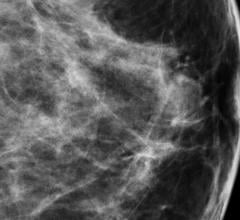

December 18, 2012 — The addition of 3-D breast imaging, or tomosynthesis, to standard digital mammography significantly increases radiologists’ diagnostic accuracy while reducing false positive recall rates, according to the results of a multicenter study published in Radiology.

A new three-dimensional (3-D) digital mammography technique has the potential to significantly improve the accuracy of breast cancer screening, according to a study published in Radiology.